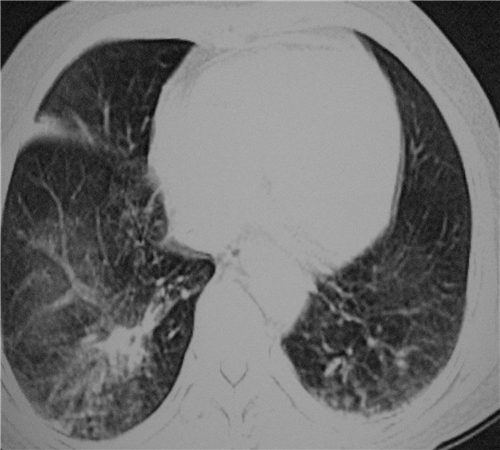

标题: CT26849:女67岁反复胸痛两天余,临床考虑夹层。

右肺感染,未见夹层。

既然考虑夹层,建议强化!另:右下肺感染!

1)右肺感染性病变。2)建议行ct增强扫描或mri检查排除主动脉夹层。

双下肺感染,右侧显著。有无夹层,增强扫描后再诊断。

1.考虑双肺感染,右侧为重;2.建议ct增强或mri排除主动脉夹层